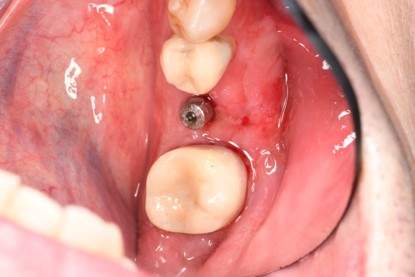

症例写真-2

- Befor

- 途中経過

- After

| 年齢 | 50代・男性 |

|---|---|

| 主訴 | 右下歯が疼く |

| 治療内容 | ・右下6番インプラント ※1:FGG(遊離歯肉移植術)とは、足りない歯ぐきを上顎から上皮を切り取り移植する外科手術 |

| 治療費 | 合計:902,000円(税込) ■内訳 |

| 治療期間 | 9ヵ月 |

| 治療方針 | 右下の当該歯は歯根破折により保存不可能と診断しました。歯周疾患も伴っていたため抜歯後に骨吸収※1が大きく起こることが予測できました。チタンメッシュ併用骨再生誘導法(GBR※2)を選択しインプラント埋入と同時に行い自然な歯槽骨のラインを再現しました。またGBRを行う際にインプラント辺縁の付着歯肉の減少が起こる為、遊離歯肉移植術(FGG※3)を行い清掃性を考慮した形態に仕上げました。 ■治療方針の解説 治療した右下の歯をレントゲンで撮影したところ根本の部分に黒く写る箇所があり「根尖性慢性周囲炎※1」と診断。また歯周病も進行していました。 ※1 骨吸収・・・歯槽骨という歯を支える骨がなくなっていくこと |

| 担当者所見 | 主訴の右下だけでなく歯茎の腫れ、発赤があり不良補綴や不良充填など他にも治療箇所が多数ありました。プラークコントロールが不良であった為まずはブラッシング指導を行いセルフケアの重要性を理解していただくところからスタートしました。 右下6番の歯はインプラント治療を行なった結果審美的にも機能的にも患者様の満足を得ることができました。骨造成と歯肉移植も行なった為インプラントを支える十分な歯周組織の獲得ができたと思っております。 |